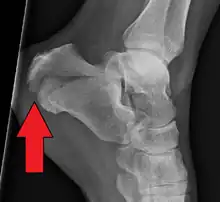

| X-ray of a fractured calcaneus | |

Conventional radiography is usually the initial assessment tool when a calcaneal fracture is suspected. Recommended x-ray views are (a) axial, (b) anteroposterior, (c) oblique and (d) views with dorsiflexion and internal rotation of the foot. However, conventional radiography is limited for visualization of calcaneal anatomy, especially at the subtalar joint. A CT scan is currently the imaging study of choice for evaluating calcaneal injury and has substituted conventional radiography in the classification of calcaneal fractures.[13] Axial and coronal views are obtained for proper visualization of the calcaneus, subtalar, calcaneocuboid and talonavicular joints.

The Angle of Gissane, or "Critical Angle", is the angle formed by the downward and upward slopes of the calcaneal superior surface. On a lateral radiograph, an angle of Gissane > 130° suggests fracture of the posterior subtalar joint surface. Böhler's angle, or the "Tuber Angle", is another normal anatomic landmark seen in lateral radiographs. It is formed by the intersection of 1) a line from the highest point of the posterior articular facet to the highest point of the posterior tuberosity, and 2) a line from the former to the highest point on the anterior articular facet. Böhler's angle is normally 25° to 40°.[14] It is named after Austrian physician Lorenz Böhler.[16] A decreased angle is indicative of a calcaneal fracture.